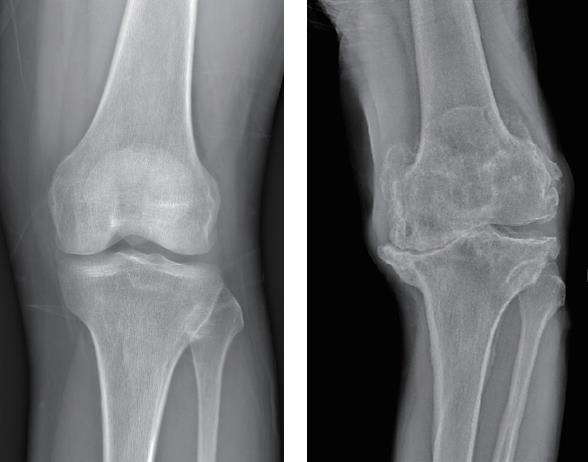

图1-6 正常膝关节与慢性膝关节骨关节炎对比(X光片)

注:左图是正常膝关节,右图是慢性骨关节炎患者的膝关节。可以看到,正常膝关节在X光片下显示均匀的关节间隙,这是由健康的关节软骨造成的。而慢性膝关节骨关节炎患者的膝关节间隙消失,关节周围骨赘形成,还出现了关节变形。